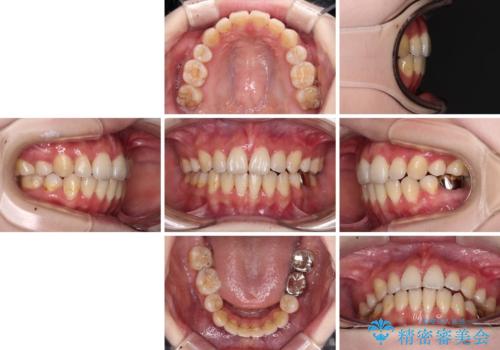

- 口元の突出感を気にして来院された患者様です。

上下左右の第一小臼歯4本を抜歯して口元を下げる治療計画としました。

裏側矯正特有の抜歯スペースに前後の歯が倒れ込む状態が長く続き、改善に長期間を要しました。